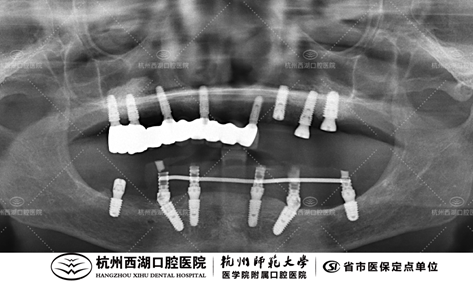

种植团队采用All-on-6即刻修复技术,为张阿姨植入6颗种植体,即日戴牙完成半口修复。

术后CBCT照如下